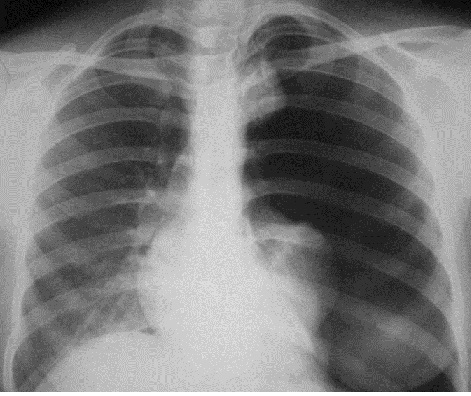

Затемнения могут отображать патологические процессы, поражающие дольку (очаговые тени) (рис. 4), больше чем дольку, но меньше сегмента (фокус затемнения), сегмент или долю (ограниченное затемнение) (рис. 5); большую часть легкого или соответствующей половины грудной клетки (обширное или субтотальное затемнение) (рис. 6). Очаговые тени разделяются на мелкие – до 4 мм в диаметре (поражения ацинуса), средние – 5-10 мм в диаметре (поражения нескольких ацинусов) и большие – 11-15 мм (поражения всей дольки).

Рис. 4. Рентгенограмма органов грудной полости в прямой проекции. Справа в верхнем легочном поле очаговые тени различного размера. Морфологический субстрат – очаговый туберкулез.